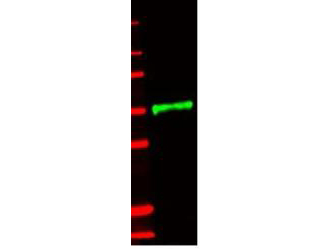

| Description | Anti-Human IL-1 Receptor Type II (IL-1RII) (RABBIT) Antibody |

| WB, IP, E |

| Application Note | ELISA 1:1,000-1:2,000 Western Blot 1:500-1:2,000ImmunoPrecipitation:1:400-1:800 |

| Purity | This antiserum is directed against the extracellular domain of the human IL-1R type II, but precipitates the intact receptor expressed on human cells. In general, this antibody also detects primate IL-1RII. The antibody does not recognize human IL-1, IL-1Ra or IL-1R type I. In ELISA formats and other immunoreactive assays, this antibody will detect the extracellular domain of the IL-1R type II (also called soluble IL-1R type II) found in human body fluids, particularly in the circulation, urine and supernatants of cells and synovial fluid. |